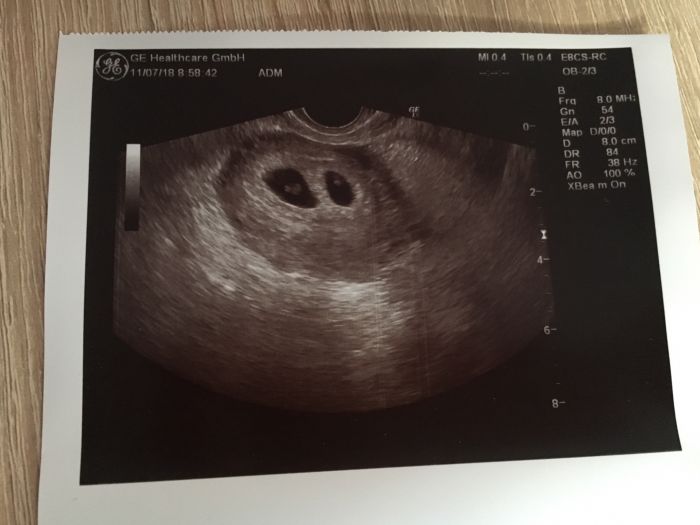

[1091491] jeeee ty jsou krásné ❤️ Také čekáme dvojčátka dvojvaječné, také jsme byli trochu v šoku. Kontrola byla 11.7 a další až 15.8 už se nemůžu dočkat a doufám že bude vše OK. TP máme zatím 6.3.

Cauky holky mám dotaz. Dnes jsem byla na první kontrole a mám takové smíšené pocity a tím ze to je první mimi tak se chci zeptat na vaše zkušenosti.. když pominu ze tam na mě všichni koukali tak jakoze co ty tu ve 21 děláš.. doktor mě doslova serval na dvě doby začal mít řeči o rakovině a ze jsem tam měla byt ještě před tím než jsme mimi zkusili, ze je snad jasne ze se jde nejdřív k doktoroj a pak až se pokouší.. (nidky jsem neměla žádné problémy) a k mimi mi jen řekl je tam srdce bije.. a fotecku jsem si musela vyprosit.. mate někdo zkušenost s podobným jednáním? Přemýšlím zda nemám změnit doktora protože místo nadšeni jsem šla pryč skoro se slzama.. Dekuju P.S. Přidávám vyprosenou fotecku ?